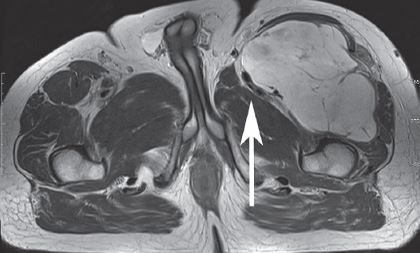

This MRI shows a large mass on the upper left hand side of the thigh (upper right hand side of the image) which is compressing the muscles and nerves.